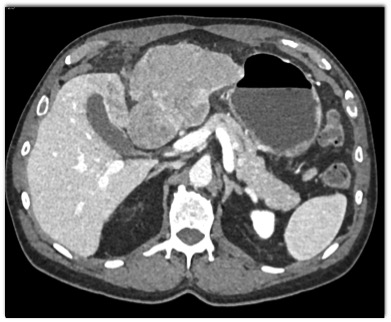

The best diagnosis in this patient with right upper quadrant pain is?

Gastric adenocarcinoma

GIST tumor of the stomach

Hepatoma

Cholangiocarcinoma